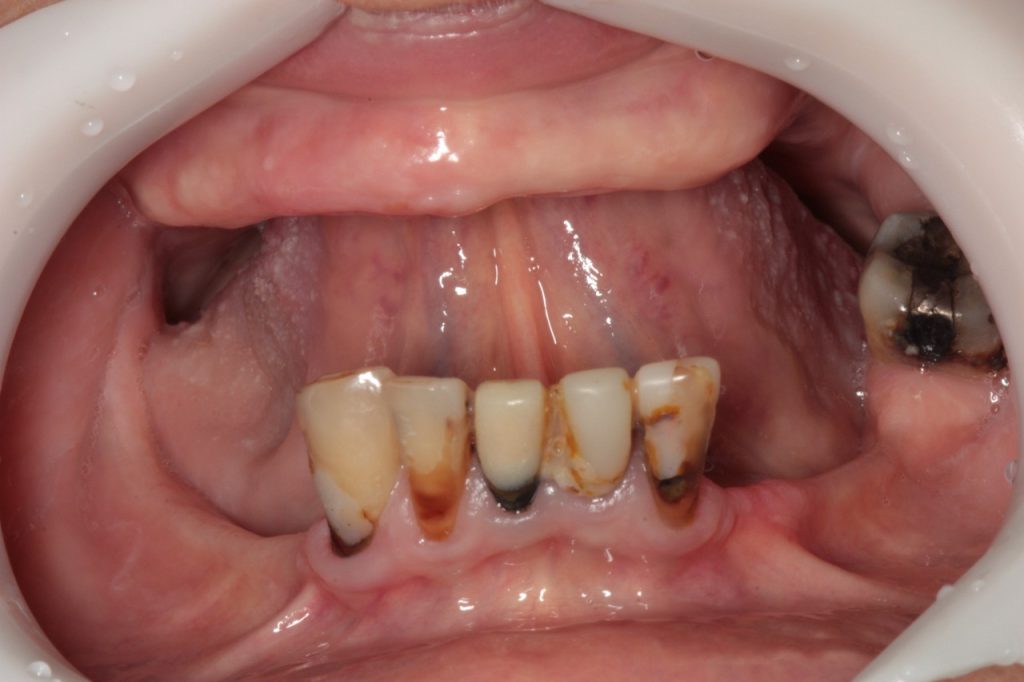

Indicados para casos extremos de reabsorção óssea, onde os implantes tradicionais não têm ancoragem, temos a grata satisfação em oferecer a reabilitação com os implantes zigomáticos. Isto é possível através da nossa equipe especializada de cirurgiões bucomaxilofaciais e médicos, que devolvem o sorriso fixo mesmo nos casos limítrofes.